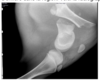

Une génisse angus de grande valeur génétique est présentée avec une boiterie de non appui du membre postérieur gauche avec enflure. Difficultés à se lever et beaucoup d’enflure dans la région. Voici la radiographie, lequel est vrai : a) Le clou verrouillé est une méthode d’immobilisation à éviter dans ce cas b) Fixateur externe de type 2 est facile à implanter permettant une grande liberté de mouvement c) Ce veau est particulièrement susceptible de développer des maladies néonatales d) Les tiges intramédullaires sont le traitement de choix avec excellent pronostic e) La béquille de thomas est la méthode de choix pour immobiliser cette fracture

**c) Ce veau est particulièrement susceptible de développer des maladies néonatales** ## Footnote => Parce qu’ils ont de la difficulté à se lever et à se tenir debout,l’ingestion de colostrum est souvent insuffisante. =>ttt= Administration de plasma ou de sang entier si absence d’immunité passive. **=Tiges intramédullaires insérées de façon rétrograde = Clou intramédullaire**